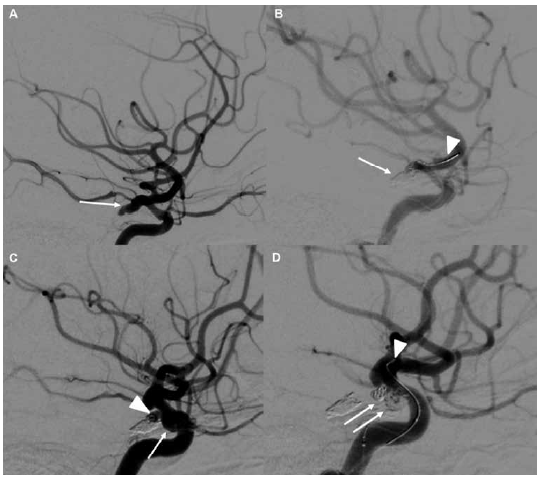

La técnica endovascular empleada con mayor frecuencia fue la de remodeling en un 39 % de los casos, seguida del diversor de flujo en un 25 %. El número promedio de coils utilizados fue de 1,9/aneurisma. Para el coiling, se logró un grado I de RROC en el posoperatorio inmediato en 24 casos (60 %). No se encontró significancia estadística entre el estado de ruptura y el resultado angiográfico inmediato (p = 0,10). Se realizó seguimiento en 18 aneurismas (45 %) tratados mediante coiling: 12 casos (67 %) presentaron RROC grado I y 5 casos (28 %) RROC grado II (Tabla 3). Para el diversor de flujo, se logró un grado D de OKM en el posoperatorio inmediato en 7 casos (33 %). Todos los aneurismas tratados con diversor de flujo fueron no rotos. Solo 2 aneurismas (13 %) fueron seguidos, con grado D en el 100 % de los casos. En total, se realizó un seguimiento del 37 % de los aneurismas, con una media de 11 meses (Tabla 4).

Varios trabajos reportaron resultados similares en cuanto al resultado clínico y angiográfico, dado que nuestros resultados angiográficos inmediatos alcanzados fueron RROC I en 60 % y RROC IIIa en 35 % de los casos. A pesar de que tuvimos un seguimiento del 37 %, más del 90 % de los casos lograron una oclusión completa o casi completa (RROC I y RROC II). Además, el 76 % de los pacientes tratados presentaron una buena evolución, especialmente en los aneurismas no rotos y el 57 % en los aneurismas rotos.